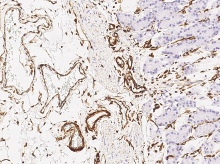

Anti-Vimentin antibody

(Cat#: 100254-R001)

How tumor exosomes communicate cancer progression

Immunochemical staining of human Vimentin in human stomach. Image Credit: Sino Biological Inc.